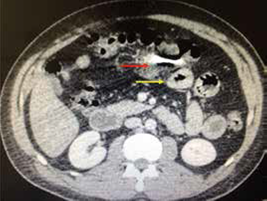

En la figura 1 se esquematiza la conducta tomada en los 62 pacientes a quienes se les practicó TC. En 14 pacientes, se indicó la cirugía por los hallazgos de la tomografía: en 5, las lesiones estaban localizadas en la cara anterior del abdomen, en 4, en la zona toracoabdominal izquierda, en 2, en la cara posterior del abdomen, en 2, en el flanco izquierdo, y en 1, en la pelvis. Los hallazgos tomográficos que sugerían lesión en este grupo de 14 pacientes fueron, en orden de frecuencia, trauma de órgano solido con sangrado activo (28,5 %), perforación del tubo digestivo (28,6 %), ruptura del diafragma (7,1 %) y trauma vascular (7,1 %) (figuras 2 y 3). Los hallazgos tomográficos y quirúrgicos en ellos se muestran en la tabla 1.

En este mismo grupo de 14 pacientes operados, 12 tuvieron lesiones que requerían manejo quirúrgico; en dos (el 4 y el 8), la laparotomía no fue terapéutica (figuras 4 y 5); en tres, el abdomen no se pudo evaluar, aunque había estabilidad hemodinámica, por lo cual se les practicó TC; el número 1 tenía politrauma, llegó intubado y sedado a la institución, al igual que el número 12; el número 2 tenía trauma raquimedular asociado.